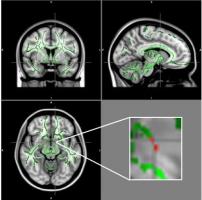

OBÉSITÉ à l’ADOLESCENCE : La perturbation de l’appétit se lit dans le cerveau